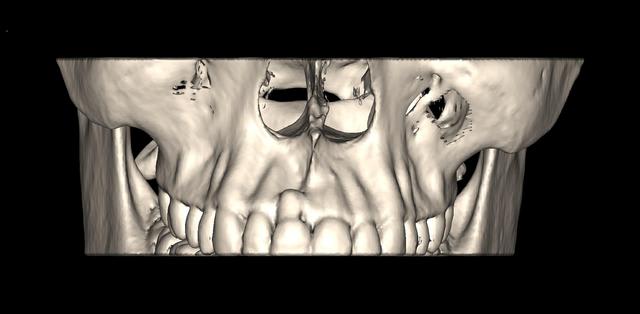

encore un ptit cas...sympa si on veut...car là j'ai besoin de l'expérience de ceux qui font çà souvent...

patient 17 ans...bientôt 18...

trauma dans l'enfance sur 11 et 21

pour la 21, çà va...mais la 11 est à bout de souffle...avec l'apex qui traverse la gencive vestibulaire...

veut un implant...forcément...mais là, faut une greffe...plutôt importante...

je pencherais plutôt pour un bloc fixé avec des vis d'ostéosynthèses...par contre, je suis pas chaud (et lui non plus) pour aller prélever au menton ou sur la branche montante...